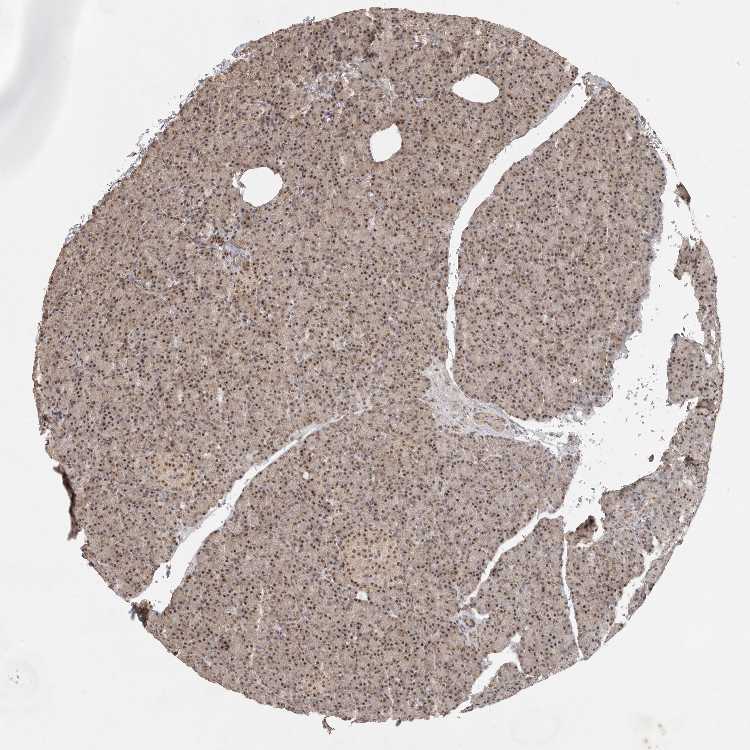

PANCREAS - Antibody stainingi

Antibody staining in the annotated cell types in the current human tissue is reported as not detected, low, medium, or high, based on conventional immunohistochemistry profiling in selected tissues. This score is based on the combination of the staining intensity and fraction of stained cells.

Each image is clickable and will lead to virtual microscopy that enables deeper exploration of all samples and also displays staining intensity scores, fraction scores and subcellular localization as well as patient and tissue information for each sample.

Antibody HPA026995

Exocrine glandular cells Medium

Pancreatic endocrine cells Medium